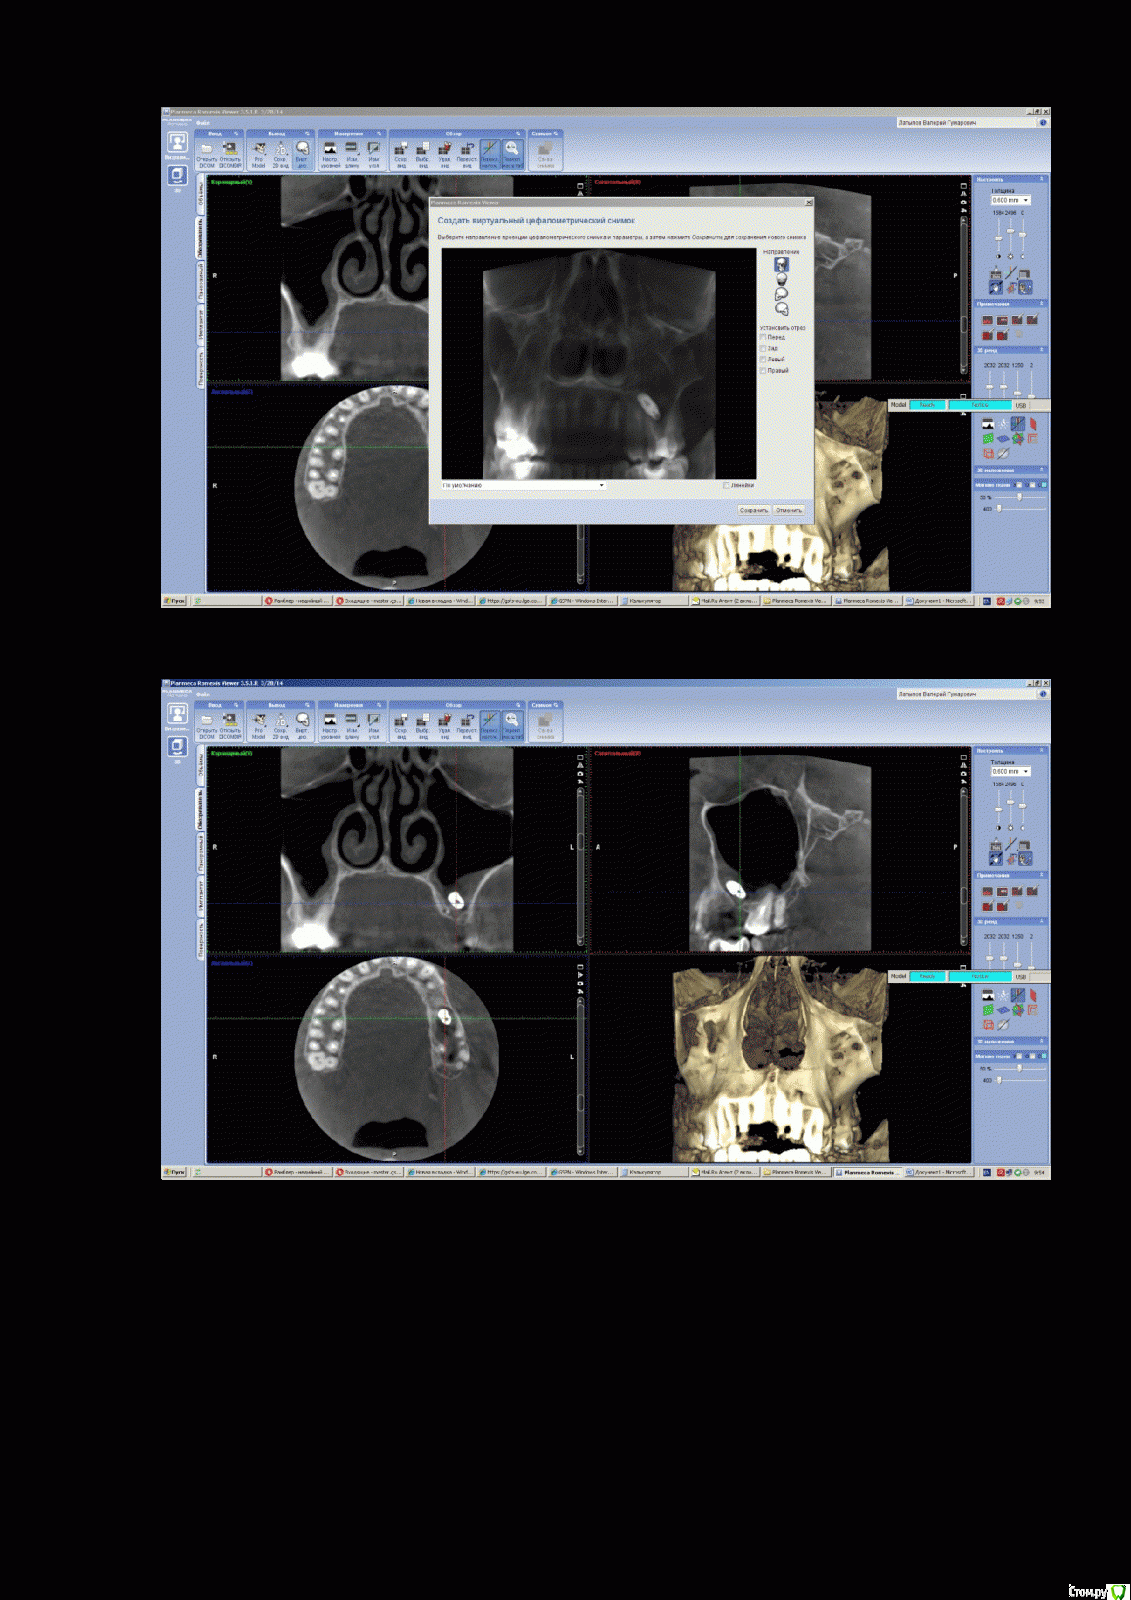

VELICOPTER Опубликовано 8 февраля, 2016 Поделиться Опубликовано 8 февраля, 2016 Добрый день,3 года назад имплант ушёл в гайморовую пазуху (снимок прилагаю) никак не беспокоит.Сейчас озадачился вытащить его,стоматолог предлагает совместить операцию по вытаскиванию импланта с синус лифтингом,подскажите,так можно делать ?Какова вероятность осложнений?Или вообще его не трогать? Ссылка на комментарий

VELICOPTER Опубликовано 9 марта, 2016 Автор Поделиться Опубликовано 9 марта, 2016 8 дней назад удалил имплант,оказался вообще в др. стороне,операция была сложной(3 часа), врач не мог найти имплант,делали повторно снимок.Синус сделал-но сказал,что результат не гарантирует,отёк спал,швы рассосались. Ссылка на комментарий